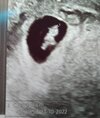

Dziewczyny‼‼‼ ja już po wizycie!!!! Ależ jestem szczęśliwa!!! Jest moja mała fasolka i i jest pięknie bijące serduszko❤❤❤

Wszystko jest w porządku, zgadza się prawie co do dnia bo z USG wychodzi 6+5, termin porodu 24.10. Fasolka ma 0,81cm.

• IMG_20220304_155051.jpg

IMG_20220304_155051.jpg

632,8 KB · Wyświetleń: 72